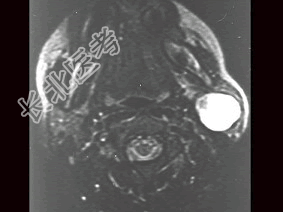

- [材料题] 女性,30岁,左侧腮腺无痛性包块5个月,无面瘫,触诊肿块质韧,表面光滑。大小约6×8厘米,B超示腮腺浅叶实性肿块 ,均质,包膜完整。患者相片及影像资料见下图。